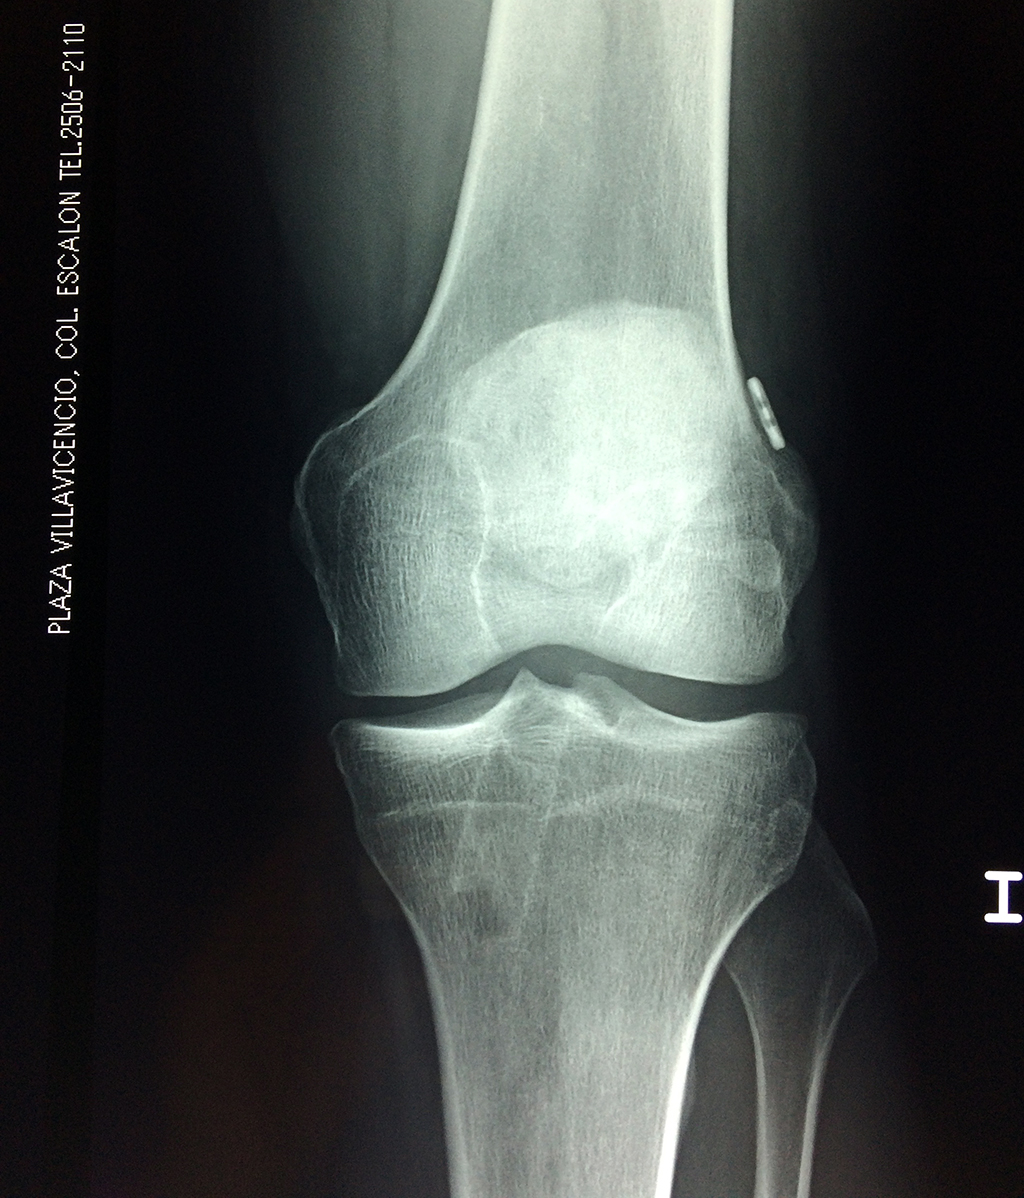

La artroscopia de rodilla es un cirugía en el cual la estructura interna de la articulación es examinada ya sea para realizar un diagnostico o para realizar un tratamiento, este procedimiento se realiza utilizando un instrumento parecido a un pequeño tubo llamado artroscopio.